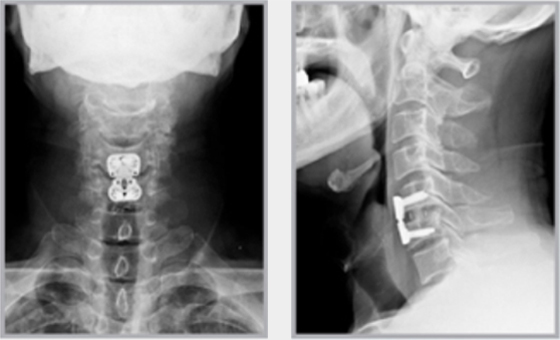

목디스크란 목뼈 사이에 있는 디스크가 손상되어 신경을 압박하는 질환을 의미합니다. 디스크는 젤리와 같은 수핵과 섬유륜으로 구성되어 있습니다. 섬유륜이 손상되면 수핵이 밖으로 밀려나와 신경을 압박하게 됩니다.

목디스크는 주로 잘못된 자세, 과도한 스트레스, 외상 등으로 발생합니다. 잘못된 자세로 장시간 컴퓨터를 사용하거나 운전을 하면 목에 무리가 가고 디스크가 손상될 수 있습니다.

또한 과도한 스트레스는 근육을 긴장시켜 디스크에 손상을 줄 수 있습니다. 외상은 교통사고, 운동 중 충격 등으로 목뼈가 부러지거나 골절되면 디스크가 손상될 수 있습니다.